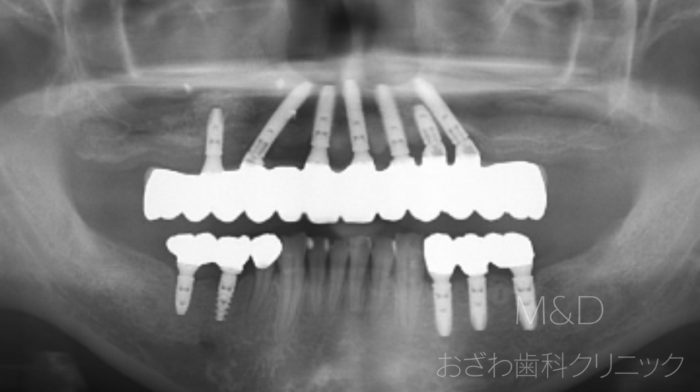

術後

上顎7本 (4本で即時負荷、その後段階的にインプラント追加)下顎5本インプラント